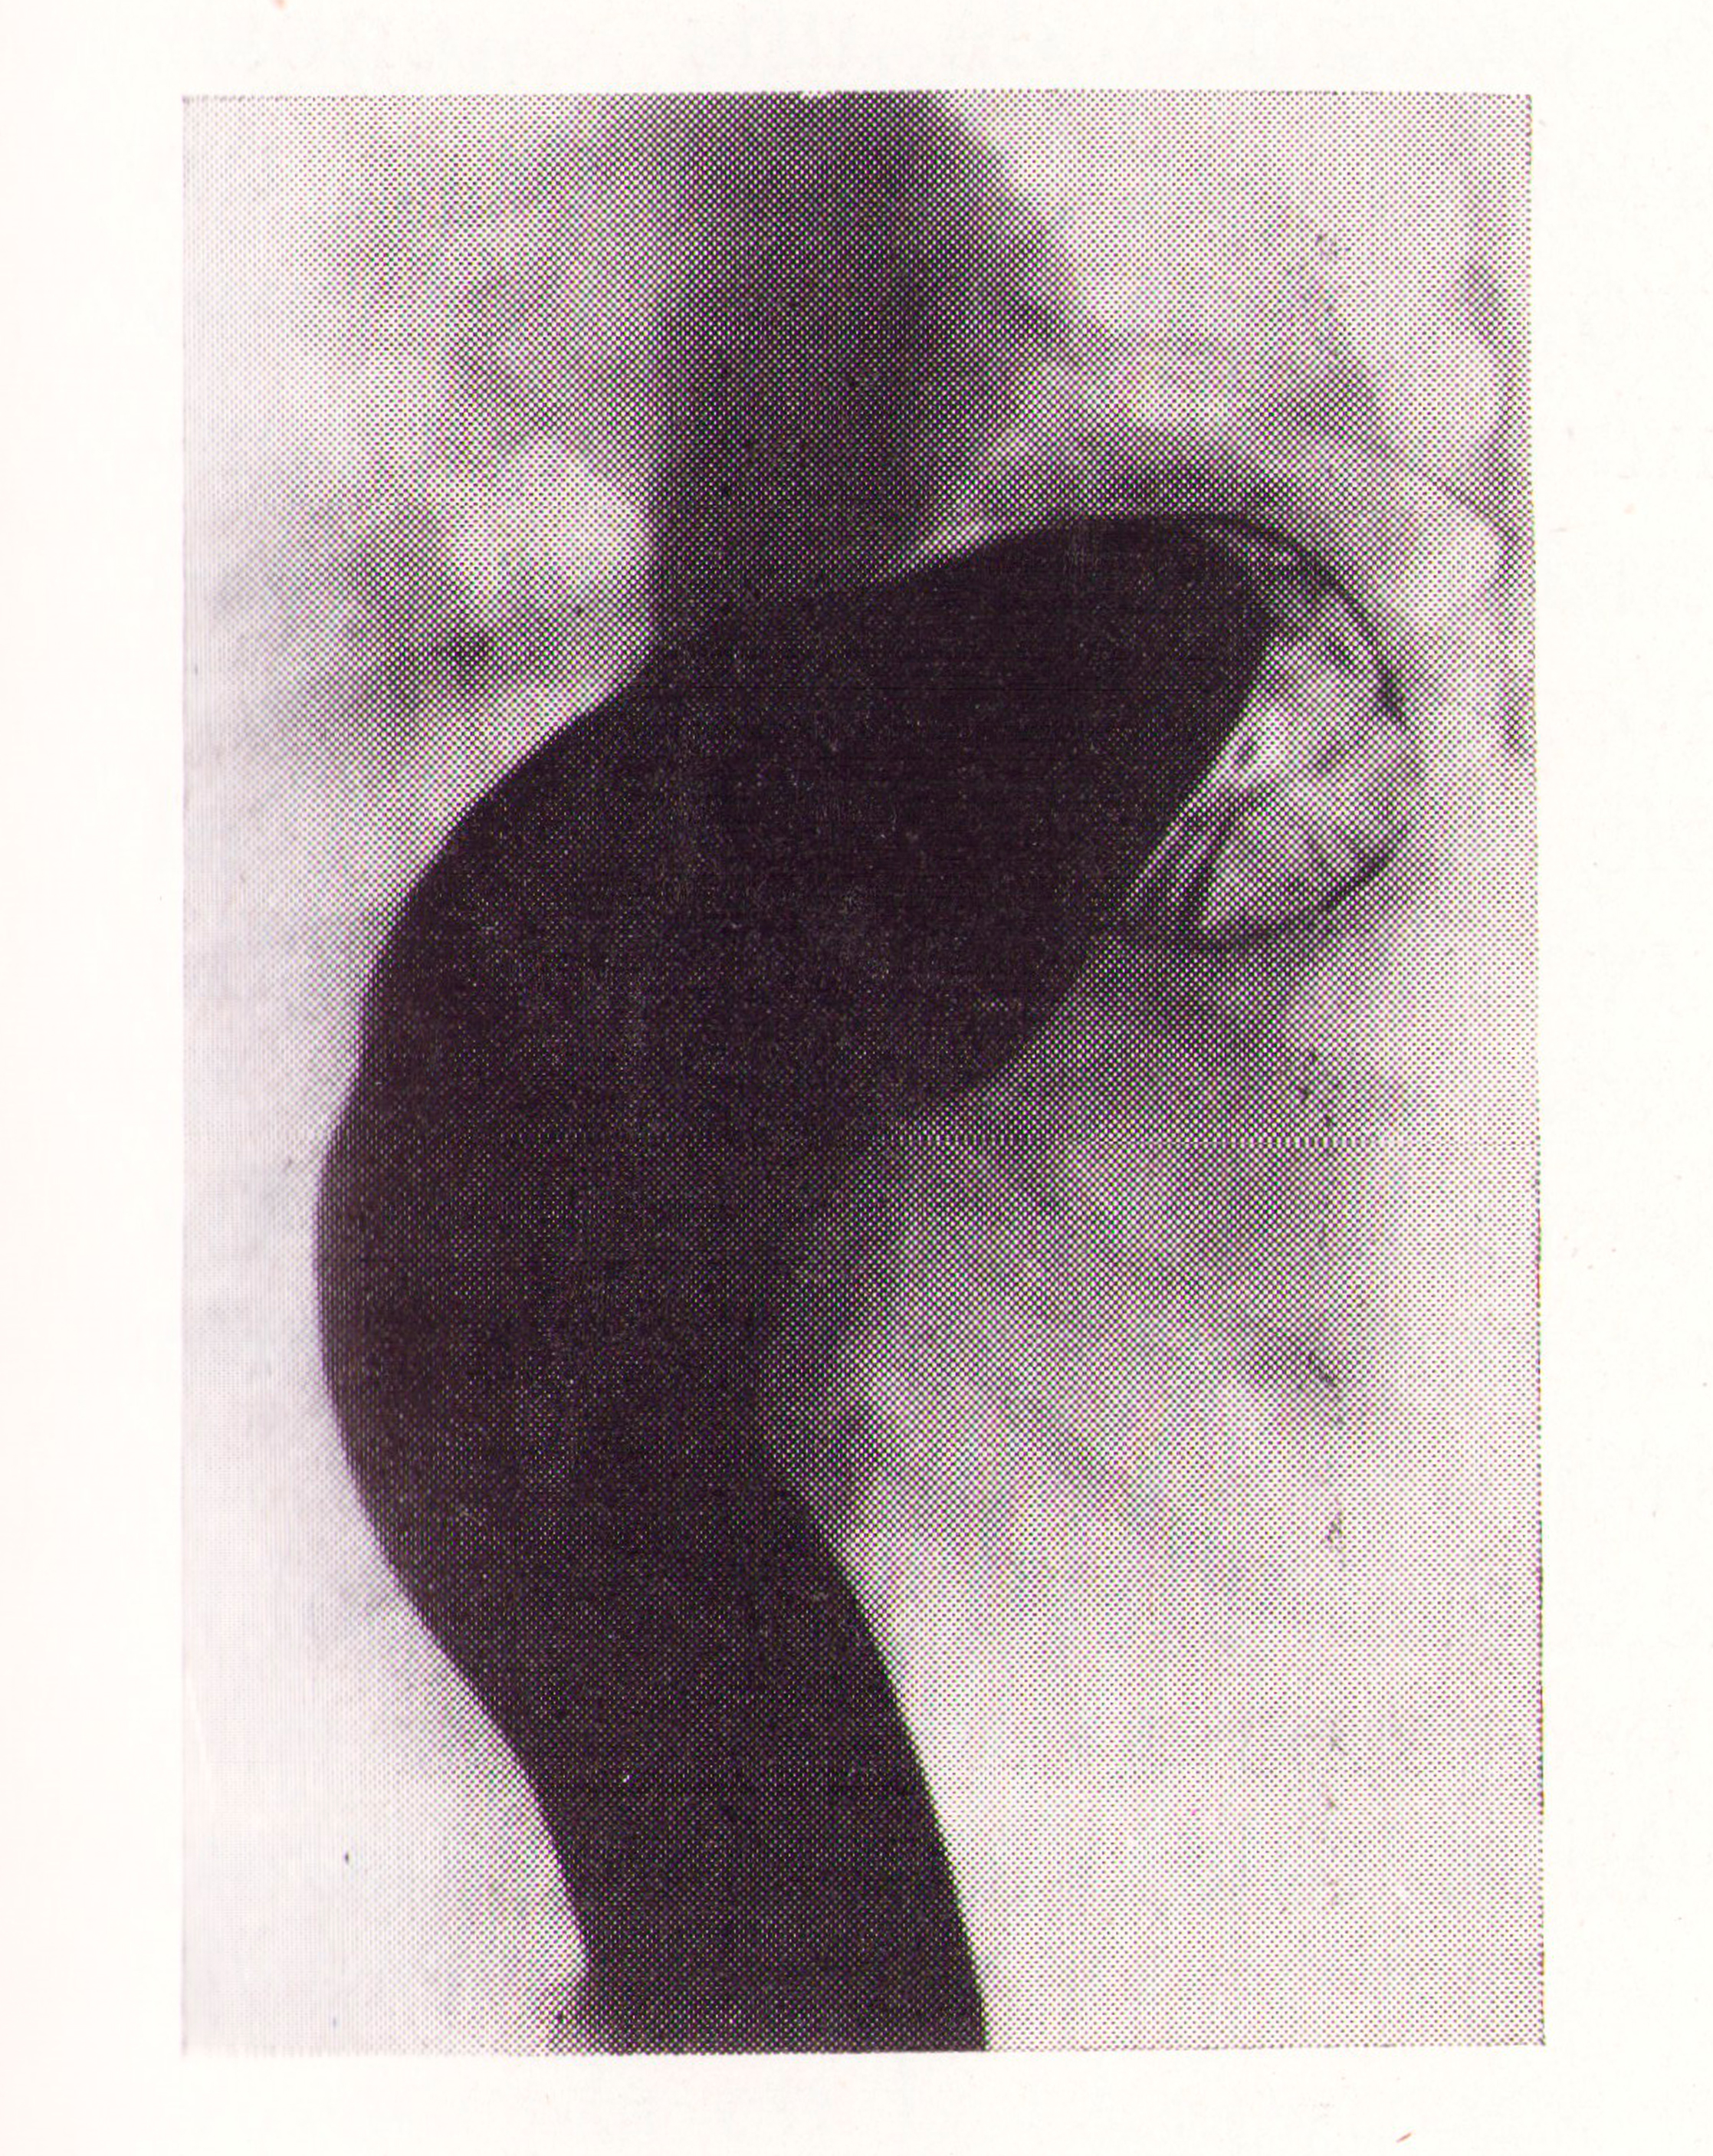

Dolicocolon izquierdo

Fig.3. Revista Española de ciencias médicas, Clínica y laboratorio, 1953.